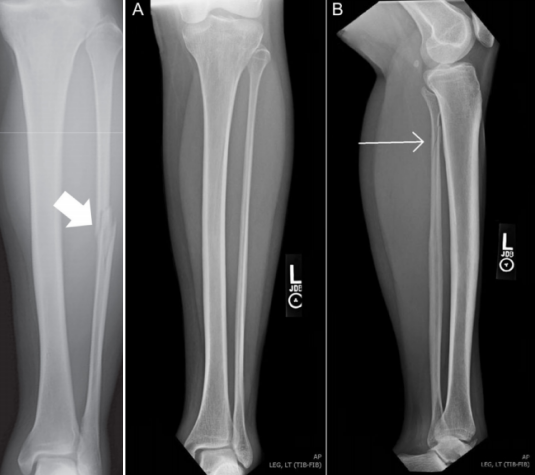

1.初次就诊时的临床漏诊率为 14.28%-44.4%。漏诊的原因主要是关注踝关节疼痛,忽视了小腿近端的疼痛,影像学检查的时候,不会刻意去关注腓骨近端的影像。当踝关节X线片未见腓骨骨折,但显示内侧结构损伤、下胫腓联合分离或合并后踝骨折,应进行腓骨近端的体格检查及影像学检查。

2.对于踝关节损伤的患者应注意对腓骨近端的查体,并行胫腓骨全长X线片。

综上,Maisonneuve骨折是容易漏诊的一种踝关节骨折,在查看患者时要特别注意小腿近端的疼痛及压痛,X片检查时尽量拍摄胫腓骨全长片。